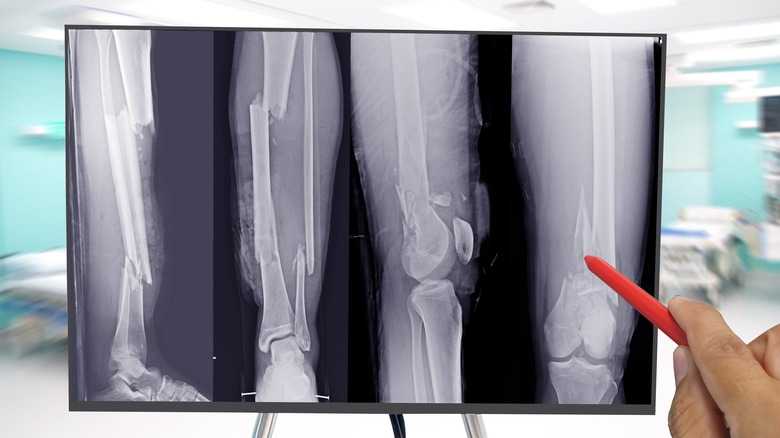

Bones fracture in different ways

Did you know that bones can break in different kinds of ways? Medical experts have names for each specific type of fracture that can happen to the bones in your body. Kid's Health by Nemours lists seven types of broken bones, and any of these types of fractured bones can be identified via X-ray. The first of these is what's known as a greenstick fracture, which is when your bone is broken on only one of its sides. Compare something like a greenstick fracture to a torus fracture, which is when the bone bends outward on one side but doesn't break on its other side. A torus fracture is also sometimes referred to as a buckle fracture.

In some cases, a broken bone will be fractured in more than two separate parts. These types of breaks are known as comminuted fracture. Similarly, there might be an injury where a bone compresses or collapses in on itself, and these types of breaks are known as compression fractures.

Doctors could also diagnose what's known as an avulsion fracture, which happens when a shard of bone is broken off by a pull from a tendon or ligament. You could also suffer a stress fracture, which is when a bone cracks instead of completely breaking. Finally, when a child breaks a bone that's in the process of growing, this is called a growth plate fracture.

Hard calluses fortified by calcium will show up on X-rays, so your doctor will be able to advise you when your healing process is far enough along that you can start to move normally on the injured part of your body.